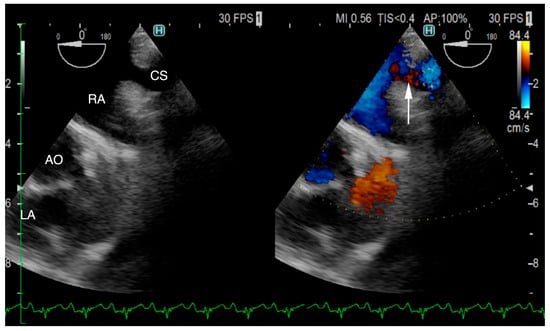

The TTE was performed using LISSENDO 880LE (Fujifilm Ltd., Tokyo, Japan) equipped with the 9–12 MHz phase array transducer probe (Fujifilm Ltd., Tokyo, Japan). TTE revealed trivial tricuspid regurgitation (TR), a pulmonary to systemic blood flow ratio (Qp/Qs) of 1.28, and there were no signs of a flattened ventricular septum. A left-to-right shunt, indicated by an irregular blood flow from the vicinity of the LA to the RA, was seen, although based on the evidence given at that time, it was possible that the blood flow was not actually within the heart. Conclusively, ASD was strongly suspected, although there was no opening found at the typical location during the TTE (Figure 1). Otherwise, the TTE evaluation revealed that other parameters were within normal limits. The results from the TTE were insufficient for a definitive diagnosis, so plans were made to further investigate with an ECG-gated CT.

Figure 1. Right parasternal long-axis four-chamber view of transthoracic echocardiography at the time of arrival. Transthoracic echocardiography shows an irregular communication between the left atrium and right atrium (arrow). From this image, it is unclear whether the blood flow is within the heart. RA, right atrium; RV, right ventricle; LA, left atrium; LV, left ventricle.